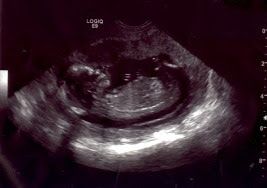

broken inside. When we’re called back, we meet doctors and nurses, I give samples of body fluids, and we do a lot more waiting. Bobby eventually leaves to feed Little H dinner and put him to bed. I continue to wait. Eventually I’m taken back to the ultrasound room where we will determine if I am, in fact, miscarrying. They put the ultrasound wand inside me and immediately I look over to the screen to see the baby squirming around, it's heart beating rapidly, and it's tiny arms flailing. Amazing!

I thought that miraculous little life had already ended, but there my baby was, moving around and making it through yet another trial.

| 13.5 weeks |